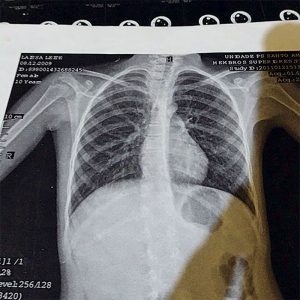

A surpresa maior foi receber o diagnóstico. “Logo no primeiro raio X, o médico falou na cara dela que era câncer de célula gigante e que não tinha cura. Não que eu não considere os especialistas, mas na hora eu, cearense, me irritei e o chamei de jumento, porque ele foi muito cruel. Ele não me chamou à parte e ela, que já estava com dor, começou a chorar e perguntou se morreria. Eu disse que faria tudo que ele mandasse, mas que não aceitaria a doença. Foi quando ele disse que eu não teria tempo, pois ela só teria dois dias de vida.”

Internada, Layssa fez todos os exames que se possa imaginar. “Ela saiu de um hospital perto de casa e, dois dias depois, foi transferida para o Hospital do Câncer (que é referência para o tratamento da doença em São Paulo)”, relata Aldelice.

Layssa passou por uma biópsia. “Tive muito medo de perder minha filha. Foi muito difícil, pois ouvimos que, como estava na clavícula, não seria possível fazer o tratamento quimioterápico. O tumor ainda poderia inchar e comprometer a respiração dela”, conta.